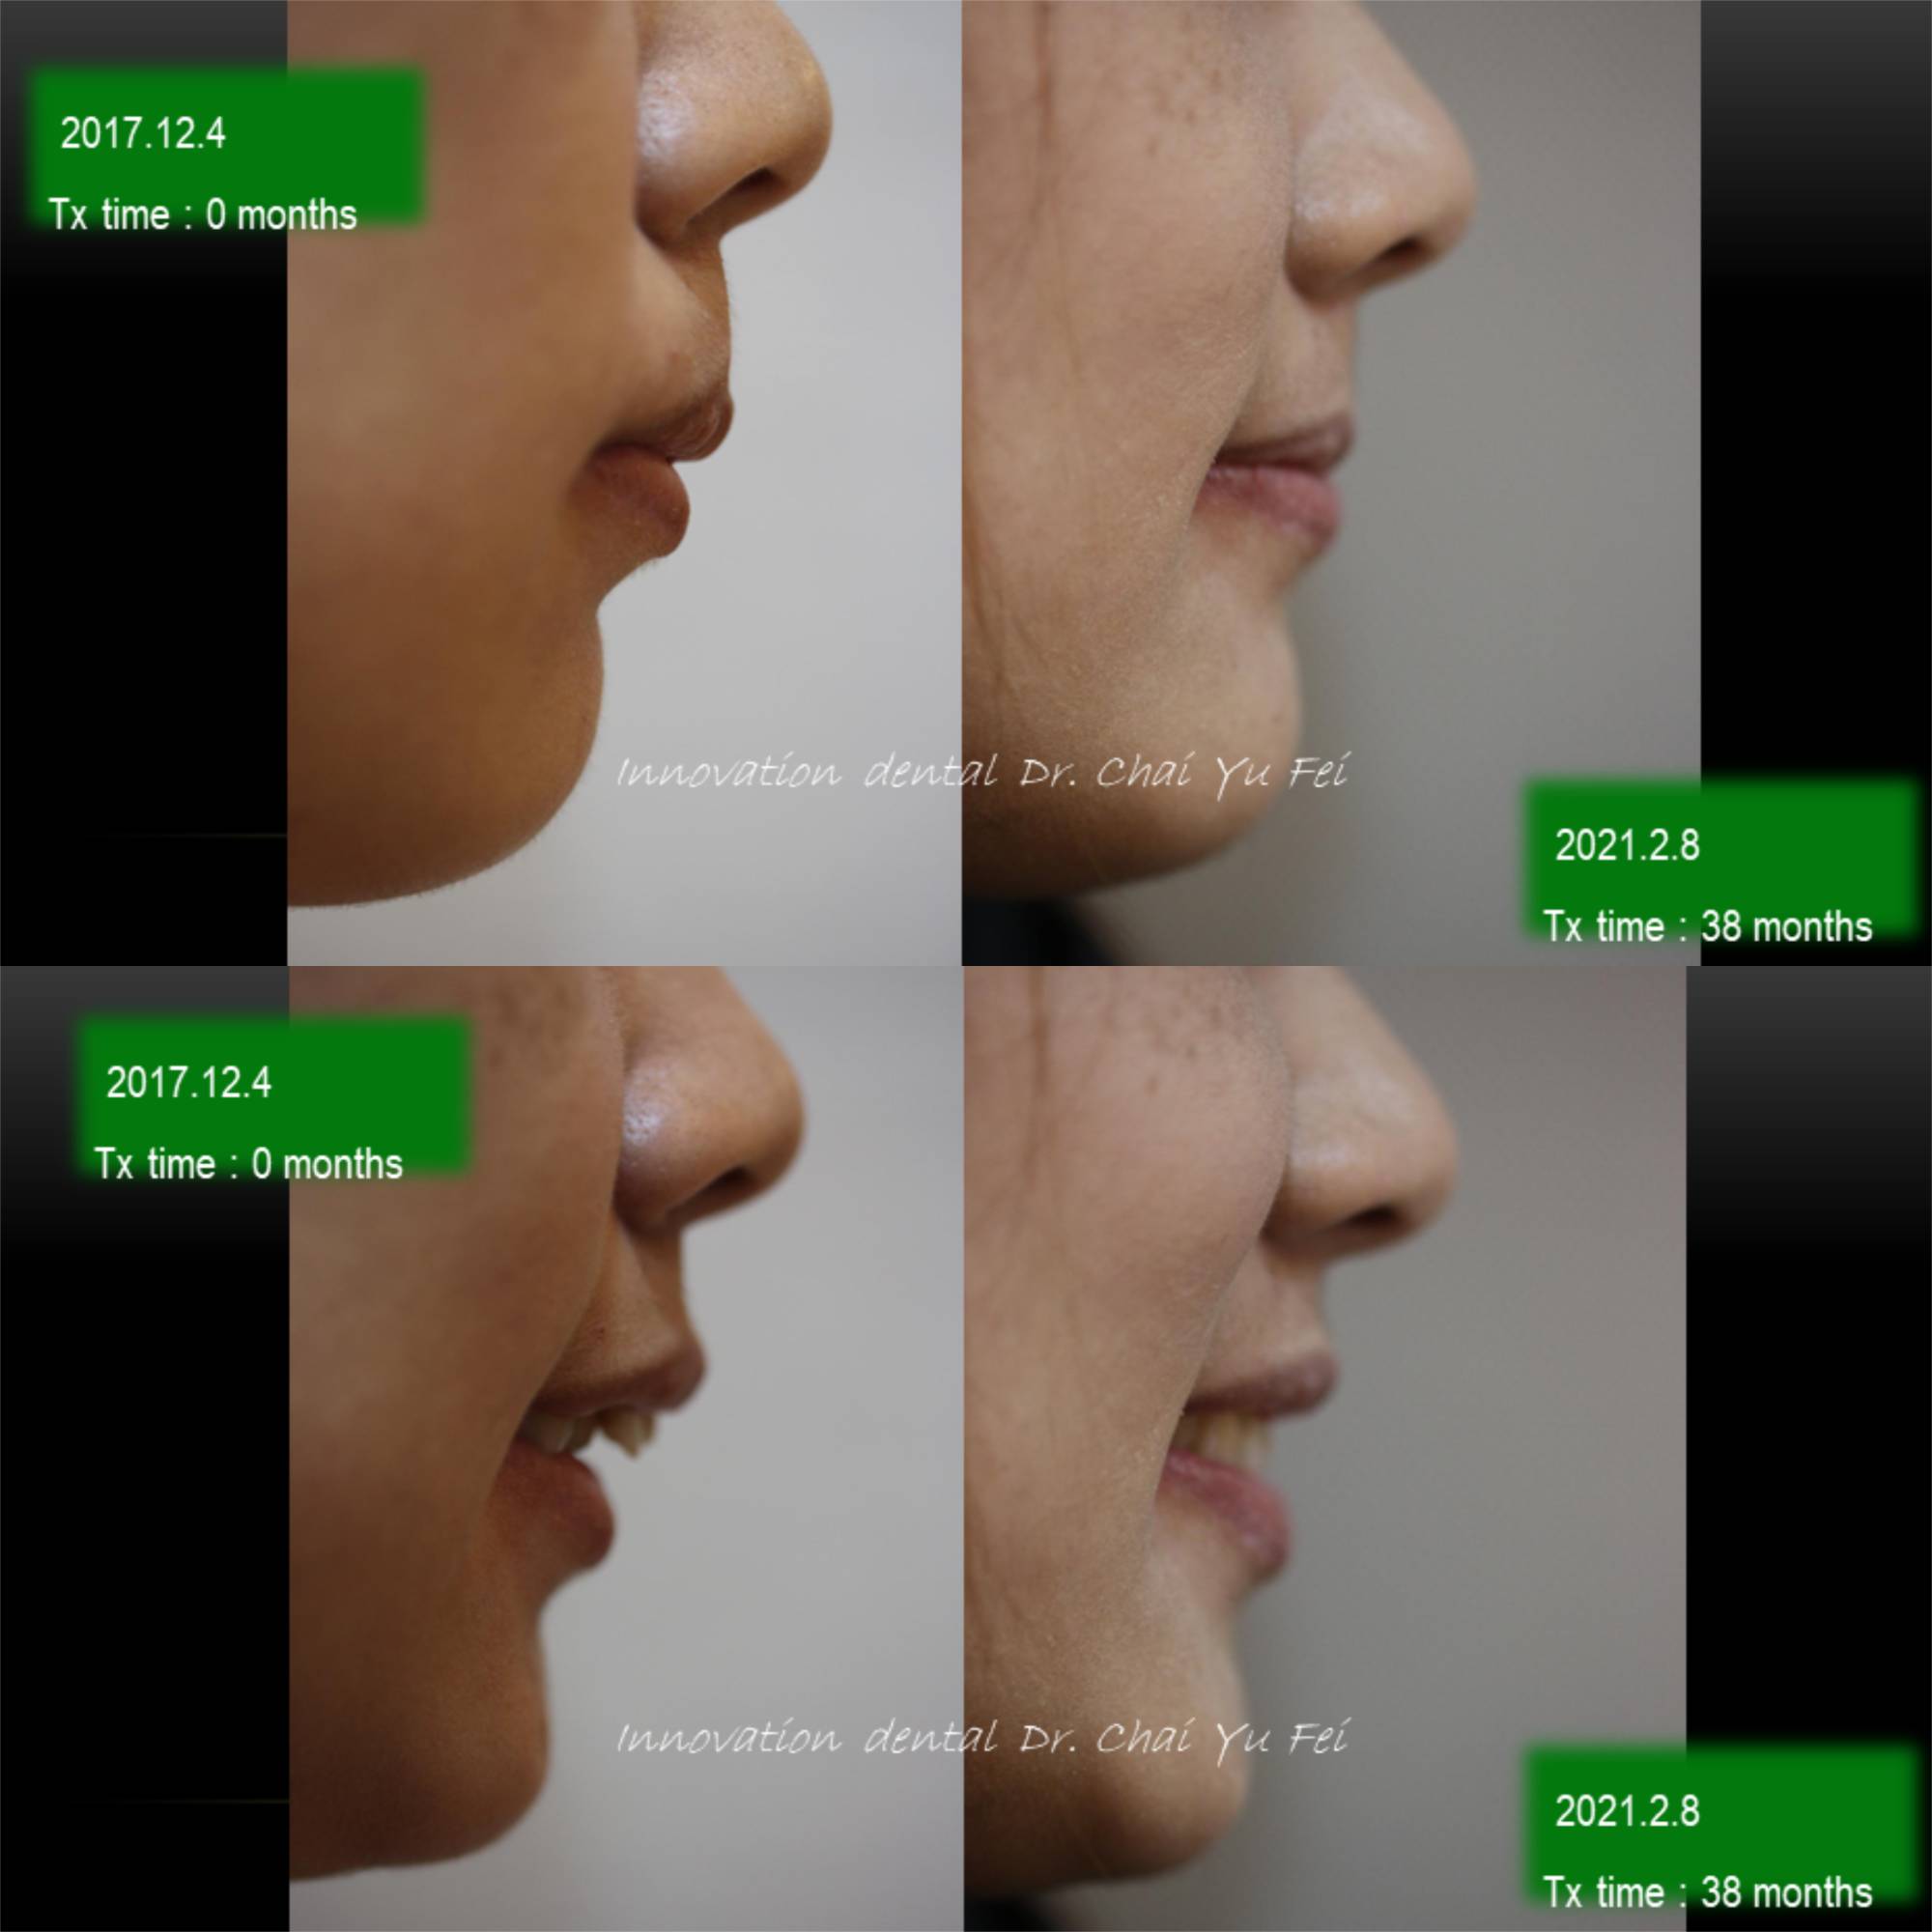

以這次黃小姐的案例來說,可以從照片中看到,由於上顎齒列狹窄,前牙角度往外傾斜,進而造成唇形前突不理想。

為了避免過度治療而傷害了原本可以恢復青春美麗的外觀,翟醫師決定採取上顎拔2顆小臼齒,下顎不要拔牙,在保留最多自然牙的情況下,改善下顎角度達到最美麗的外觀輪廓跟理想的咬合。

拔牙矯正前後變化,改善嘴型前突

看到這樣的治療結果,相信您應該對拔牙沒有那麼擔心了,不論是拔4顆或是拔2顆牙齒,我們無非都是為了讓出更多空間,來把齒列調整整齊,選擇拔牙的牙位通常也是重複性高的小臼齒,或是有病灶的牙齒,具有重要功能及不可取代性的牙齒我們不會隨便拔除,即使要犧牲牙齒,我們設計的治療計畫也會將犧牲降到最小,而且完全不影響功能以及外觀。治療完成後,一樣有好的微笑曲線跟理想穩定的咬合。

抜歯矯正治療によって、治療後では前歯の傾斜と前突が改善されたため、

上下の唇を無理やり閉じる必要がなくなりオトガイに固有の自然なカーブが現れています。